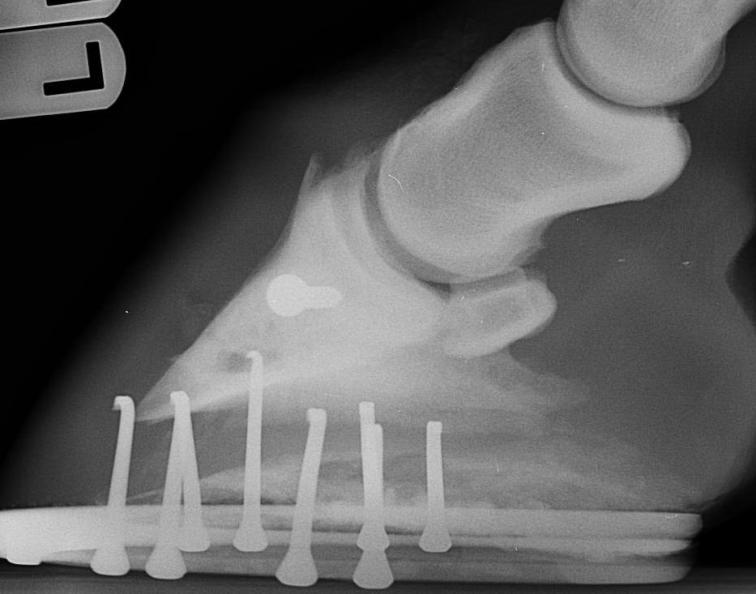

Posted on Monday, Nov 27, 2006 - 7:35 pm: here are her xrays February 2006 February 2006  October 2006 October 2006  February 2006 February 2006  October 2006 October 2006  February 2006 February 2006  October 2006 October 2006

Posted on Tuesday, Nov 28, 2006 - 6:30 am: Welcome Anthony,I do have a few questions before we get into rehab. First what is the filly doing now? I am also interested in the prognosis you received from the surgeon after the last set of radiographs? I am concerned because the last lateral radiograph distinctly shows periarticular changes consistent with osteoarthritis and, more subjectively, is the narrowing of the joint space compared with earlier images. DrO |

Posted on Tuesday, Nov 28, 2006 - 10:19 am: Here's a close-up:

Posted on Wednesday, Nov 29, 2006 - 7:07 am: Nice images Anthony but my concerns are not allayed. Notice in the first image what appears to be a joint mouse at the top of the coffin joint space? The periarticular osteophyte is at the insertion of the coffin joint capsule onto the coffin bone. I have to wonder if this area will put up with the stress of running full out for several minutes. But take heart I suspect the surgeon is a better judge of what is possible here than I am Anthony.My next consideration is the screw that remains. I am not familiar with racing with such an appliance in place and maybe it is done all the time o object. I would discuss with the surgeon the problem of a object that does not move like the surrounding bone when placed under intensive exercise and consider having it removed as it may weaken the bone. Following removal I would wait 6 more months before beginning training. You should train and possibly race this horse with a bar shoe. One study found a significant decrease in the incidence of refracture in racing horses with previous coffin fractures when bar shoes are used. I think your rehab schedule is reasonable in consideration of what the horse is doing now. I have mixed feelings about the triamcinolone acetonide injections but think I might choose this route in your place since there are already signs of DJD. Following its use you have a transient period where the joint will not respond as well to the stresses of exercise. If you decide to do them I would give the horse a 3 week pasture rest following the injections before continuing training. Once you begin breezing in earnest I like the 21 day steps as long as the horse is getting 2 to 3 contiguous days rest each week to allow the skeletal system to respond to that weeks exercise. DrO |

Posted on Thursday, Feb 15, 2007 - 6:52 pm: From the radiographs the bone appears to be healing and there is minimal increase in evidence of DJD in the coffin bone but none of this tells us if the horse is sound, how is the horse doing soundness wise?DrO |